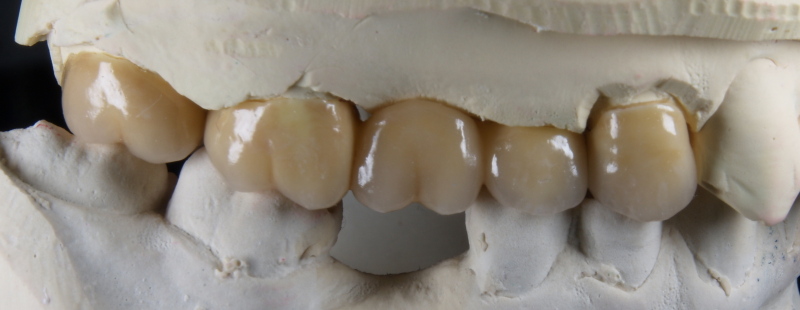

Vom Langzeitprovisorium zur TEK 1 Arbeit